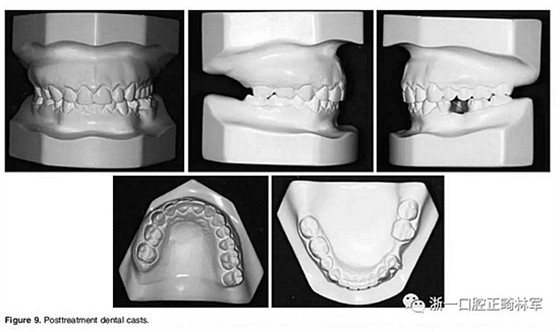

在治療結(jié)束時,面部基本對稱(Figure 7)。上中線與面中線重合,下中線向左偏0.5mm,傾斜的合平面得到矯正,獲得了良好的咬合關(guān)系,具有正常的覆合和覆蓋,留下7mm的空間用于植入左下前磨牙(Figure 8、9)。

全景片顯示牙根平行度良好、無吸收。此外,在左下第二前磨牙的區(qū)域獲得了用于植入種植體修復(fù)的良好空間。頭顱側(cè)位片和疊加顯示,上下切牙傾斜度以及前后和垂直向位置的變化也很大(Figure 10、11; Table 1)。